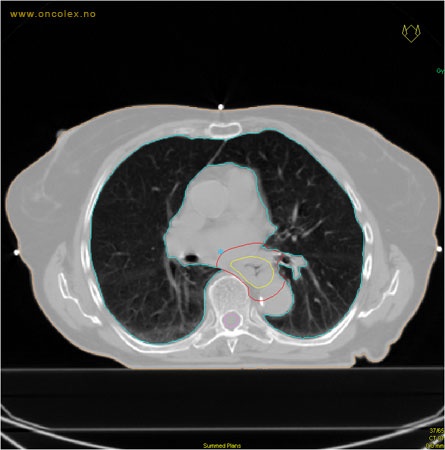

Målvolum

Skisse over hvordan strålefeltet planlegges:

Illustrasjon for målvolum

• GTV (Gross Tumor Volume): Identifisert tumor.

• CTV (Clinical Target Volume) GTV + omkringliggende vev hvor det kan væremikroskopisk spredning.

• ITV (Internal Target Volume): CTV + en indre margin som tar hensyn tilindre bevegelser og endringer av CTV.

• PTV (Planning Target Volume): Innstillingsmargin som inneholder ITV og samtidig tar hensyn til antatte pasientbevegelser, samt variasjoner i pasientopplegging og feltinnstillinger.

• Feltgrense. Tegnes som oftest på kroppen.

ICRU (International Commission on Radiation Units and Measurements)